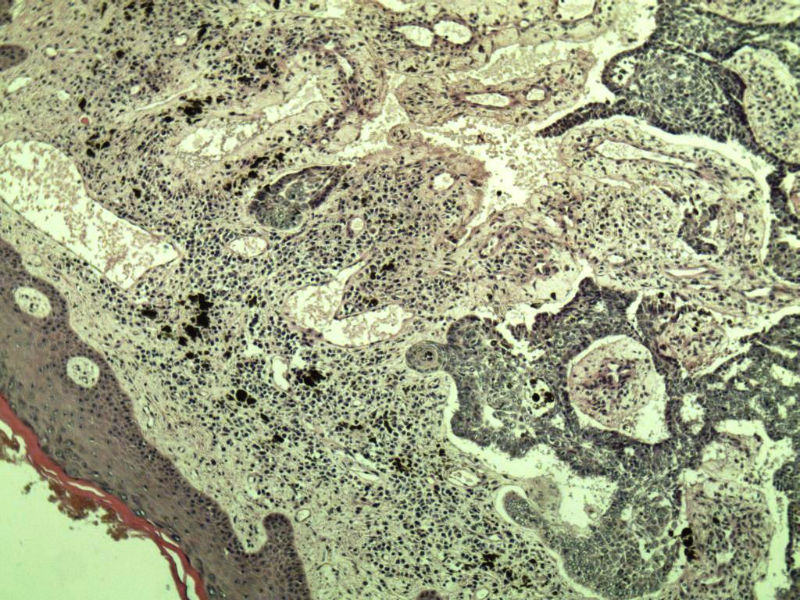

女 67岁 临床考虑面部色素痣 1*0.8 cm  请问各位老师 这是什么? 谢谢!面部包块图1

毛母/发细胞瘤鉴别基底细胞癌,可做CD10,CK7,CK20鉴别

考虑毛发上皮瘤,需除外基底细胞癌。

毛发上皮瘤,需与基底细胞癌鉴别

第一例:毛发上皮瘤

第一例:毛发上皮瘤,与基底细胞瘤区别明显。

第一例  毛发上皮瘤,和基底细胞癌鉴别一下

第一例考虑毛母细胞瘤,第二例考虑基底细胞癌。

毛母细胞瘤

第一例:毛母细胞瘤;第二例:基底细胞癌

第一例,毛发上皮瘤;第二例,基底细胞癌。

一毛发上皮瘤